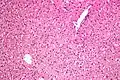

In liver pathology, a ground glass hepatocyte, abbreviated GGH, is a liver parenchymal cell with a flat hazy and uniformly dull appearing cytoplasm on light microscopy. The cytoplasm's granular homogeneous eosinophilic staining is caused by the presence of HBsAg.

The appearance is classically associated with abundant hepatitis B antigen in the endoplasmic reticulum, but may also be drug-induced.[1][2] In the context of hepatitis B, GGHs are only seen in chronic infections, i.e. they are not seen in acute hepatitis B.

Micrograph showing ground glass hepatocytes. H&E stain.